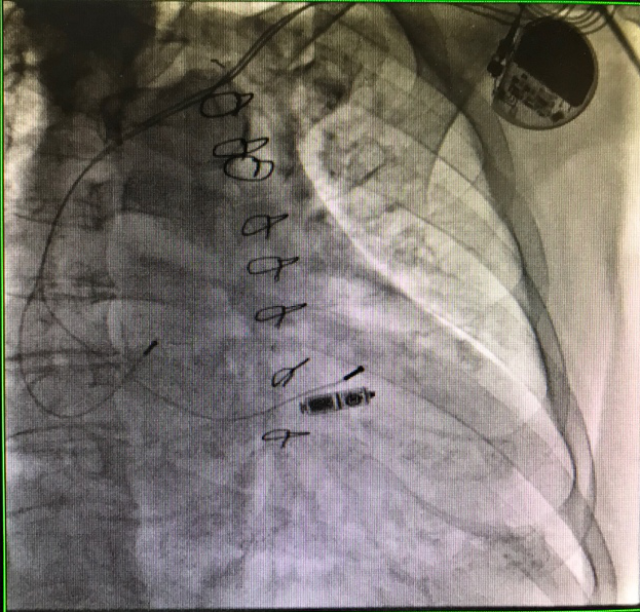

无导线起搏器及原导线